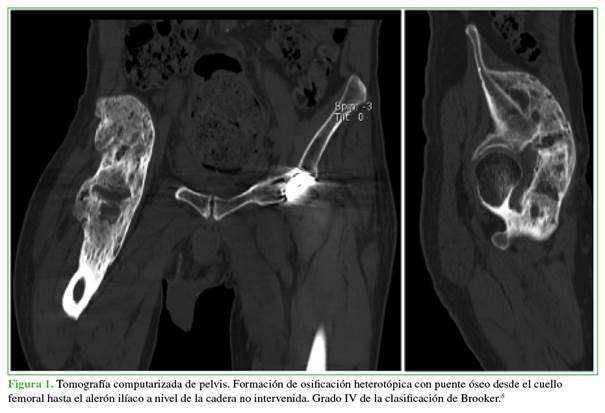

Fue derivado para su evaluación por el equipo especializado en cadera. En los seguimientos radiográficos, se observó una formación de OH con puente óseo desde el cuello femoral hasta el alerón ilíaco a nivel de la cadera no intervenida. Esta afección se clasificó como una OH grado IV de Brooker, y se había desarrollado como resultado de la inmovilidad y la hemiplejia, y provocó anquilosis y una contractura que limitó la flexión a 45°, lo que, a su vez, dificultó la sedestación, la movilización independiente y la marcha.

Se solicitó una tomografía computarizada de pelvis para planificar el manejo; además, el paciente fue evaluado por los equipos de Fisiatría y Anestesiología (Figura 1).

La tomografía computarizada optimiza la planificación preoperatoria al proporcionar una visualización tridimensional mejorada de la OH en relación con puntos anatómicos relevantes. En ciertos casos, puede ser necesario recurrir a una resonancia magnética para definir, con mayor precisión, el alcance del compromiso neurovascular o de los tejidos blandos locales. Estos estudios resultan más eficaces cuando la OH se localiza próxima a estructuras anatómicas dentro del potencial campo operatorio.14